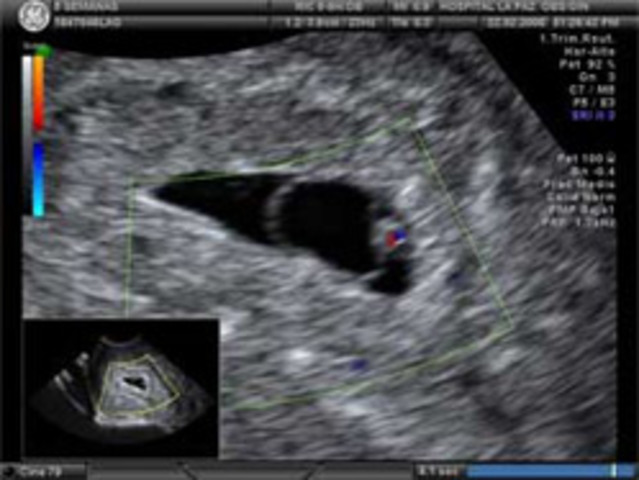

El corazón del bebé comienza a latir y el embrión ya se hace evidente. Desde el punto de vista embriológico el extremo superior (cefálico) de la columna vertebral (conocido por ahora como tubo neural) se cierra al final de esta semana y el embrión empieza a adquirir una forma de media luna, de hecho, parece un animalito con cola. El bulto central es efectivamente el corazón y ocupa casi el 25% del embrión.